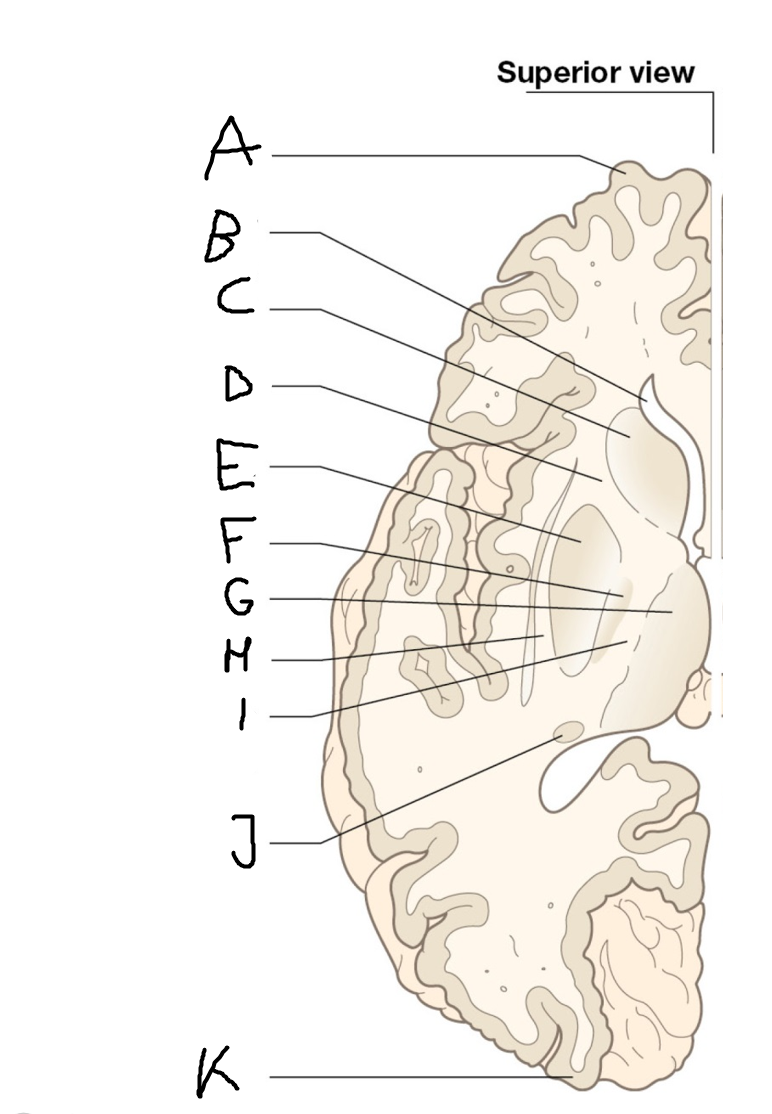

internal capsule (posterior limb)

B

anterior horn of lateral ventricle

C

head of caudate nucleus

D

internal capsule (anterior limb)

E

putamen

F

globus pallidus

G

Thalamus

H

External capsule

I

internal capsule (posterior limb)

J

tail of caudate nucleus